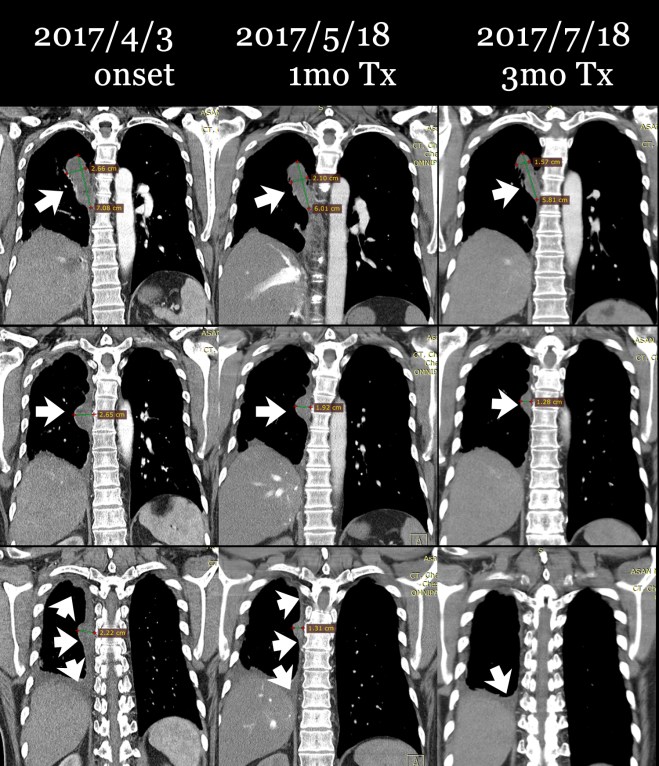

다음은 이 환자의 초기 2017년 4월 3일 CT와 이후 내원하여 4월 17일부터 한약 복용하고 한 달 뒤인 5월 18일 사진, 그리고 치료 3달 뒤인 7월 18일 사진을 coronal view (세운 채로 쪼갠 사진으로 앞에서 뒤로 단면이 cut된 사진)를 제시해 보면 확연히 종양이 줄어드는 것을 알 수가 있다. 그리고 또한 pleural thickening도 많이 감소된 것을 보게 된다. 비록 아산 소견서는 별 변화 없는것처럼 들었다고 하였지만 이 같은 차이가 쉽게 얻어지는 것은 아니며, 한약 양약 환자와 보호자의 노력이 합쳐져서 얻어지는 것임을 명심해야 한다.

이 환자의 종양은 명확히 범주를 정하기에는 불규칙한 모양을 하고 있으나 대략 가장 크게 보이는 데를 기준으로 하여서 체적을 측정하면 (이는 전문가가 아닌 나의 측정이므로 오차가 꽤 있을 수는 있음을 양해를 구한다) 4월 3일 52CC 정도에서 한 달 치료 후에 35CC 정도로 감소되었고 또 7월 18일 마지막에는 18CC 정도로 줄었다고 볼 수 있다.

그리고 환자 분은 2017년 7월 18일 다시금 아산에서 CT를 촬영하여서 내게 방문을 하였고 역시 지속적으로 한약과 UFT를 더하자 더욱 많이 종양이 줄어든 것을 알 수가 있었다.

이 환자의 종양은 윗부분은 확연히 사라지고 가장 크기가 넓은 데가 1.6×4.2cm에서 1.38×3.69cm 로 다소 줄어들어 보인다. 체적으로 대비하면 꽤 줄었다고 볼 수 있다. 환자 보호자는 여전히 줄었어도 근심하는 얼굴이다. 최근에 황달수치가 1.2 기준에서 t-bil이 1.5로 상승하였기 때문에 한약 때문인가 걱정을 하였다. 나는 절대로 그럴 일은 없다고 이야기하였다. 체질에 안 맞으면 모를까 체질에 맞는 약은 오히려 간기능을 좋게 한다. 그래서 되물었다. 최근에 무언가 새로운것을 먹는것이 없냐고 물었더니 내게 고지하지 않고 이웃에서 권유한 효모를 먹고 있었다. 효모는 소양인 약으로 anti cholinergic 한 효과가 있다. 소음인에게서는 담즙배설을 억제시키고 담관의 괄약근을 수축시킨다. 아마도 이 때문이라고 생각되어서 환자에게 이를 중지시켰다. 다음 번에 효모를 끊고 나서 다시 혈액검사를 해 보면 알 일이다. 일반인들은 이를 따지는 기전을 모르기 때문에 급한 대로 누가 효과를 보았다면 먹고 싶어하지만 암환자는 사소한 약물, 식품 하나라도 영향을 받는다. 그래서 거듭 환자에게 음식주의와 운동을 할 것을 당부하였다.